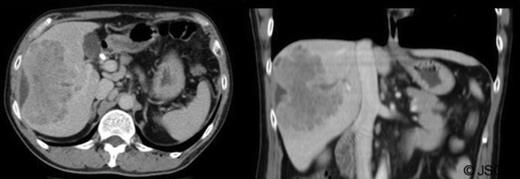

Abdominal ultrasound displayed biliary sludge although no gallstones with normal thin-walled gall-bladder. Abdominal CT-scan with contrast revealed a right liver mass involving segments V to VIII measuring 10.6cm×6cm axially and 10cm craniocaudally with mild caudate lobe hypertrophy suggesting underlying cirrhosis; intra-hepatic bile duct dilation, subcapsular fluid and lymphadenopathy (figure 1).

Tumour markers revealed elevated carbohydrate-antigen 19-9 at 807kU/L (normal <40kU/L) suggesting bile-duct disease (1) whilst α-fetoprotein was 4kU/L, within normal range. Magnetic resonance Cholangiopancreatography (MRCP) indicated filling defects in right and left bile ducts (figure 2) and portal vein thrombosis.